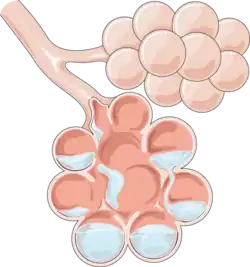

Pulmonary edema (British English: oedema), also known as pulmonary congestion, is excessive fluid accumulation in the tissue or air spaces (usually alveoli) of the lungs.[1] This leads to impaired gas exchange, most often leading to shortness of breath (dyspnea) which can progress to hypoxemia and respiratory failure. Pulmonary edema has multiple causes and is traditionally classified as cardiogenic (caused by the heart) or noncardiogenic (all other types not caused by the heart).[2][3]

The amount of fluid in the lungs is governed by multiple forces and is visualized using the Starling equation. There are two hydrostatic pressures and two oncotic (protein) pressures that determine the fluid movement within the lung air spaces (alveoli). Of the forces that explain fluid movement, only the pulmonary wedge pressure is obtainable via pulmonary artery catheterization.[10] Due to the complication rate associated with pulmonary artery catheterization, other imaging modalities and diagnostic methods have become more popular.[11] Imbalance in any of these forces can cause fluid movement (or lack of movement) causing a buildup of fluid where it should not normally be. Although rarely clinically measured, these forces allow physicians to classify and subsequently treat the underlying cause of pulmonary edema.